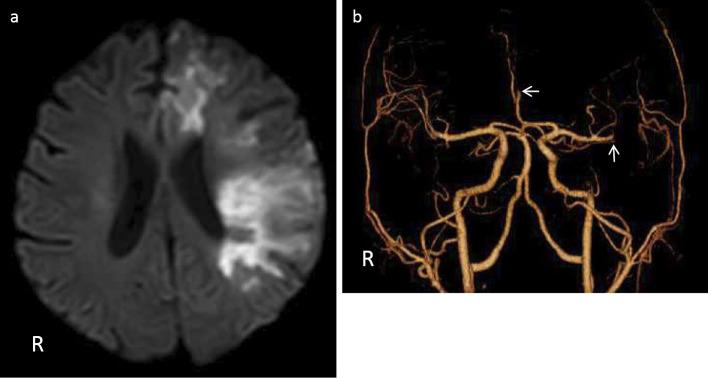

A 36-year-old man with a history of irradiation for acute lymphoblastic leukemia developed headache with cortical dysfunction lasting for 4 weeks. The clinical features were consistent with stroke-like migraine attacks after radiation therapy (SMART) syndrome. Six months later, he developed cerebral infarction due to occlusions of the left anterior and middle cerebral arteries. This is the first case report describing SMART syndrome followed by severe cerebral infarction. Although an association between the two episodes was not assumed, this case indicates that protective therapies against infarction might need to be considered for patients with SMART syndrome.

一名36岁男性,有急性淋巴细胞白血病放疗史,出现头痛伴皮质功能障碍,持续4周。临床特征符合放疗后类卒中偏头痛发作(SMART)综合征。6个月后,他因左侧大脑前动脉和大脑中动脉闭塞发生脑梗死。这是首例描述SMART综合征后发生严重脑梗死的病例报告。尽管未假定这两个事件之间存在关联,但该病例表明,对于SMART综合征患者可能需要考虑采取预防梗死的治疗措施。